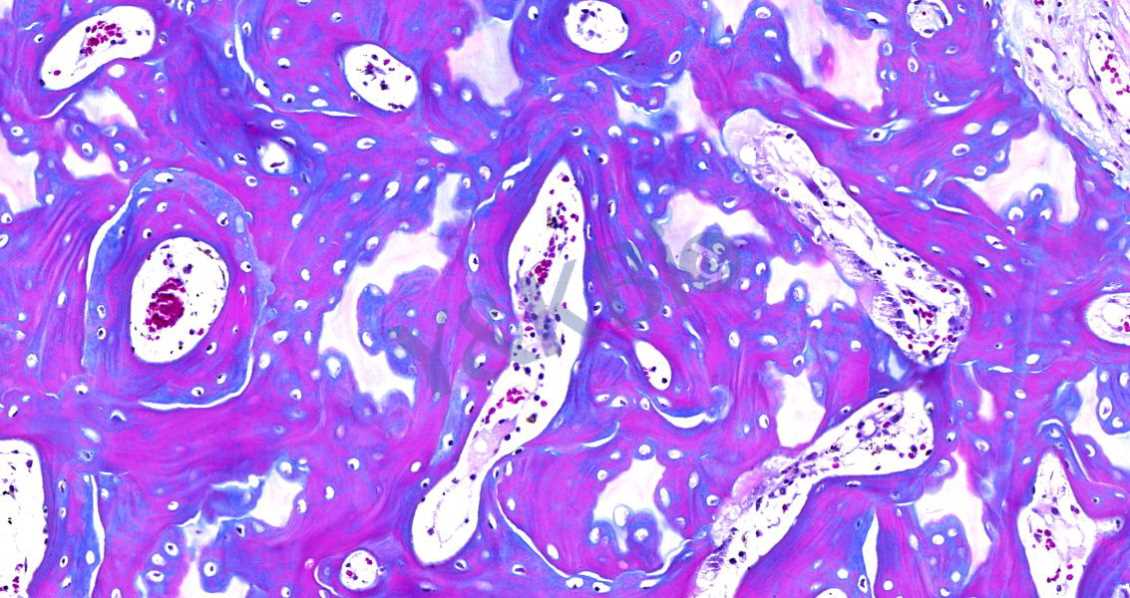

Masson染色的颜色对比鲜明,可见明显的胶原纤维网(重庆苯胺蓝染色则为蓝色,甲基绿则为绿色),能较好地反映纤维组织的形态。其中,蓝色表示新形成的骨,红色表示成熟的骨组织。

3.番红O-固绿染色

番红O-固绿染色可直观反映关节软骨、软骨下的骨组织结构,嗜碱性的软骨与碱性染料番红 O 结合呈现红色,嗜酸性的骨和酸性染料固绿结合而成蓝色,在关节软骨及软骨下骨的形态学研究中受到了欢迎。